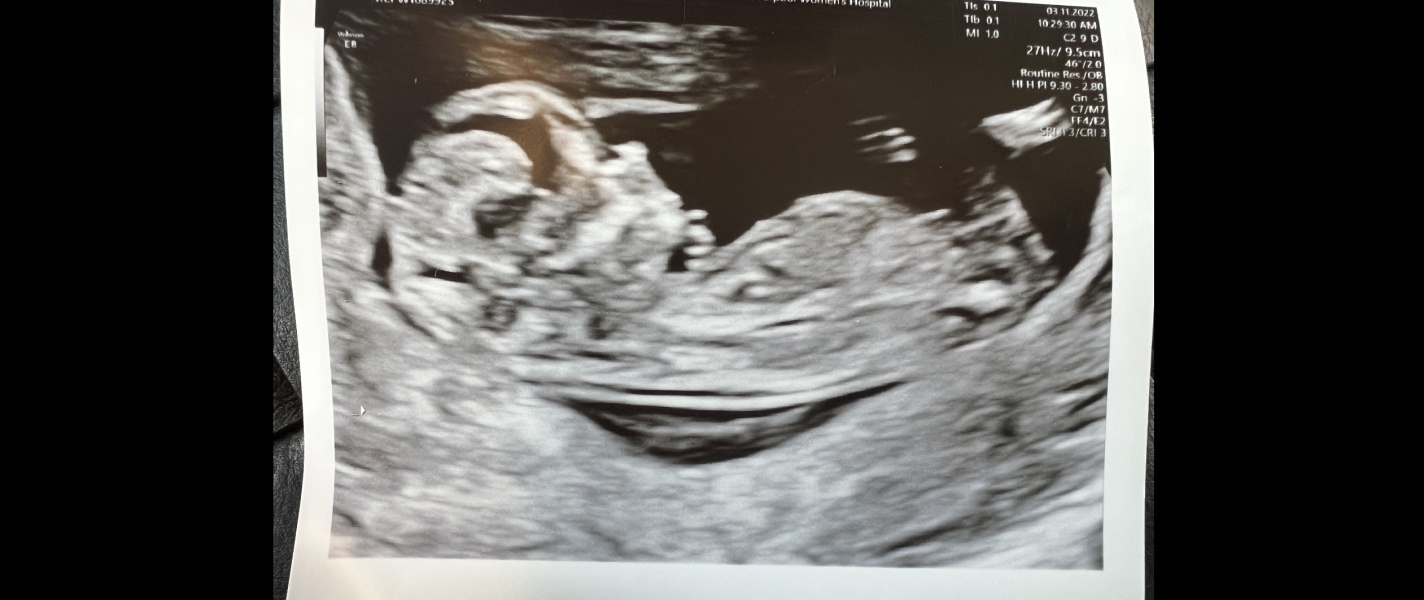

lmw88 · 01/11/2022 18:14

@raffika great to hear it went well. Always a nice relief and a bonus a little further forward than you thought. I was the opposite and put back 3 days. Hopefully wee baba has grown when I get scan next week